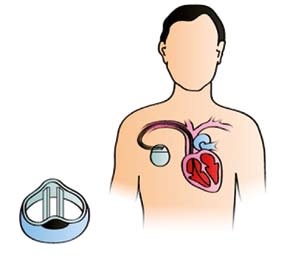

Od 60. let 20. století prodělala technologie kardiostimulátorů obrovský vývoj. Kardiostimulátory jsou menší, lehčí, pro nositele mnohem pohodlnější a jsou mnohem odolnější proti elektromagnetické interferenci (EMI). Skládají se z baterie a elektronických obvodů uložených v titanovém pouzdře. Pokud kardiostimulátor nedetekuje v pacientově srdci dostatečně silný elektrický signál, vyšle do srdečního svalu krátký elektrický proud o nízkém napětí. Přes 50 % implantovaných kardiostimulátorů dokáže upravit frekvenci vysílaných signálů podle fyzické aktivity pacienta (Allen, 2006).

Většina kardiostimulátorů je implantována při místním znecitlivění a umisťuje se pod klíční kost, mezi kůži a hrudní svalstvo. Z kardiostimulátoru vycházejí elektrody, které jsou zavedeny do srdce. Někdy je kardiostimulátor implantován do břicha a elektroda je umístěna na vnější stěně srdce (British Heart Foundation, 2005). Moderní kardiostimulátory jsou napájeny lithiumjodidovými bateriemi, které mají životnost 6–10 let. Filtry, které jsou součástí softwaru kardiostimulátoru, zajišťují velkou míru tolerance vůči EMI a další ochranu proti jejímu působení zajišťuje titanové pouzdro kardiostimulátoru (Allen, 2006). Tonks (2006) se vyjadřuje velmi skepticky, pokud jde o počet kardiostimulátorů, které jsou staženy jako vadné, a cituje statistické údaje o velkém počtu vadných přístrojů. Tonks se domnívá, že neexistují spolehlivé údaje o počtu kardiostimulátorů, které selžou kvůli vadným elektrodám, ani o počtu pacientů, kteří zemřou kvůli tomu, že jejich kardiostimulátor byl vadný. Britský Úřad pro kontrolu léčiv a zdravotnických výrobků (Medicines and Healthcare Products Regulatory Agency – MHRA, 2008) popisuje značný počet upozornění (Medical De vice Alerts), vydaných v letech 1997– 2007 kvůli vadným kardiostimulátorům, a to i od renomovaných výrobců. Vady se týkají selhání mikroprocesorů, nebezpečí selhání kardiostimulátoru, rychlé stimulace, k níž dochází, když je přístroj vypínán, a náhlé ztráty výkonu. V roce 2002 přiznal úřad MHRA problém s nedostatečným hlášením nežádoucích událostí týkajících se kardiostimulátorů a zdůraznil nutnost, aby mu technici a kliničtí pracovníci zabývající se kardiostimulátory nežádoucí události hlásili (MHRA, 2002). Fogoros (2003) uvádí, že všechny vady kardiostimulátoru se obvykle projeví brzy po jeho implantaci a mohou být zjištěny a napraveny dřív, než způsobí závažné komplikace. Symptomy, které mohou signalizovat špatnou funkci kardiostimulátoru: pacient se cítí slabý, unavený, zmámený, má závratě nebo ztrácí vědomí. V těchto případech by měl kontaktovat svého lékaře.